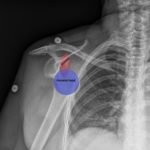

Bedside ultrasound with the transducer placed on the posterior right shoulder revealed an anterior dislocation of the right humerus. This is evident by displacement of the humeral head further away from the posteriorly placed ultrasound transducer, and appears deep to the glenoid cavity. In a posterior shoulder dislocation, the humeral head would appear closer to the transducer (and the near field of the ultrasound image) than the glenoid. Note that a hypoechoic, heterogeneous fluid collection is within the joint space, compatible with a hematoma. A right shoulder X-ray confirmed the anterior dislocation with no evidence of fracture. Under direct ultrasound guidance the glenohumeral joint space was injected with 10 mL of 2% lidocaine as an intraarticular anesthetic block. The right shoulder was reduced using continual traction. Post-reduction ultrasound demonstrated a successful shoulder reduction, depicted by the humeral head being relocated to its anatomical location, adjacent to the glenoid cavity, as noted on the ultrasound image. A hematoma remains present within the joint space. Successful shoulder reduction was further confirmed by X-ray. The patient’s arm was placed in a sling and she was discharged home with orthopedics follow-up.